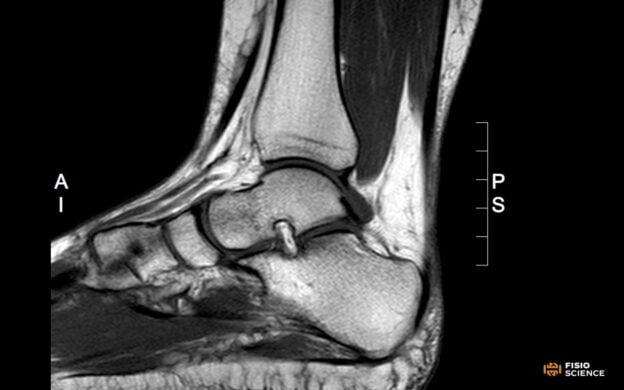

Il corso è rivolto a fisioterapisti e professionisti della riabilitazione interessati ad approfondire, dal punto di vista ortopedico, i meccanismi e le implicazioni cliniche dei traumi distorsivi di caviglia e delle lesioni legamentose croniche. Si tratta di condizioni molto frequenti, spesso caratterizzate da recidive, dolore persistente e riduzione della stabilità funzionale, con importanti ricadute sulla qualità di vita e sul ritorno all’attività sportiva. Durante il webinar verranno analizzati i principali quadri clinici e le strategie di inquadramento diagnostico, con particolare attenzione agli aspetti anatomici, biomeccanici e funzionali che guidano la valutazione ortopedica. Saranno discussi i criteri di scelta tra approccio conservativo e chirurgico, le prospettive di trattamento e il ruolo del fisioterapista nel percorso integrato di gestione del paziente. L’obiettivo è fornire ai partecipanti una visione chiara, aggiornata ed evidence-based delle problematiche legamentose croniche di caviglia, migliorando la capacità di collaborazione interdisciplinare e l’efficacia dell’intervento riabilitativo. Durata: 1 ora.